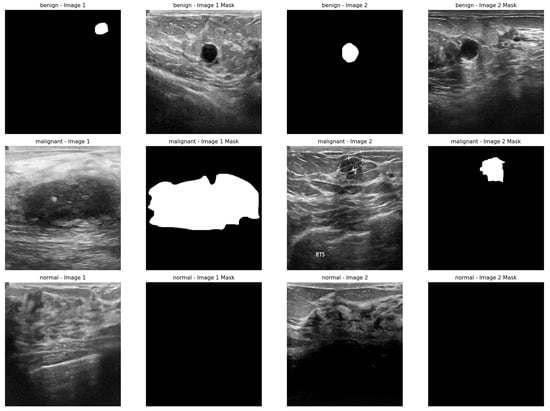

- Al-Dhabyani, W.; Gomaa, M.; Khaled, H.; Fahmy, A. Dataset of breast ultrasound images. Data Brief 2020, 28, 104863. [Google Scholar] [PubMed]